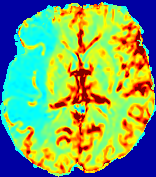

Slice #1Slice #2Slice #3Slice #4Slice #5Slice #6Dgtsuperscript𝐷gtD^{\text{gt}}Refer to captionRefer to captionRefer to captionRefer to captionRefer to captionRefer to caption(a)Refer to captionRefer to captionRefer to captionRefer to captionRefer to captionRefer to caption(b)Refer to captionRefer to captionRefer to captionRefer to captionRefer to captionRefer to caption(c)Refer to captionRefer to captionRefer to captionRefer to captionRefer to captionRefer to caption(d)Refer to captionRefer to captionRefer to captionRefer to captionRefer to captionRefer to caption(e)Refer to captionRefer to captionRefer to captionRefer to captionRefer to captionRefer to caption(f)Refer to captionRefer to captionRefer to captionRefer to captionRefer to captionRefer to captionRefer to caption000.060.060.060.120.120.120.180.180.180.240.240.240.300.300.30(mm2/s)𝑚superscript𝑚2𝑠(mm^{2}/s)

Figure 13: PIANO effectiveness and robustness testing: diffusion imaging via diffusion. Top row shows Dgtsuperscript𝐷gtD^{\text{gt}} used for simulating the ground truth pure diffusion. (a)-(f) refer to the results for D𝐷D estimated from the ground truth pure diffusion image time-series where Rician noise at levels 0%, 2%, 4%, 6%, 8%, 10% was added respectively.

Similarly, starting from the same initial condition C0superscript𝐶0C^{0} as in the ‘Advection Imaging’ experiment for each patient, we simulate concentration time-series {Cti(Ω)|i=0, 1,, 40}conditional-setsuperscript𝐶subscript𝑡𝑖Ω𝑖0140\{C^{t_{i}}\in\mathbb{R}(\Omega)|i=0,\,1,\,\ldots,\,40\} via a diffusion PDE, where we define the ground truth diffusivity D:=Dgtassign𝐷superscript𝐷gtD:=D^{\text{gt}} via the ADC map of the ISLES 2017 training set (ADC values are scaled by 0.000010.000010.00001 to ensure numerical stability):

Note this is likely not a spatially representative ground-truth for perfusion imaging, as it measures different effects from diffusion imaging. However, we still use it as a quasi-realistic pattern of diffusivity in the brain. We also added 2%, 4%, 6%, 8%, 10% levels of Rician noise to obtain simulations of ‘Diffusion Imaging’. The estimated Destsuperscript𝐷estD^{\text{est}} given concentrations of all noise levels for one patient are shown in Fig. 13, PIANO estimation results for all patients are summarized in Fig. 11 (b). Again, PIANO demonstrates its capability to recover the underlying diffusion field. In Fig. 13, when the noise level is increasing, some noisy patterns indeed appear in the associated Destsuperscript𝐷estD^{\text{est}}. Note that the ground truth diffusivity applied in this simulation experiment is about ten times larger than the diffusivity estimated in reality (Fig. 3, Fig. 4).